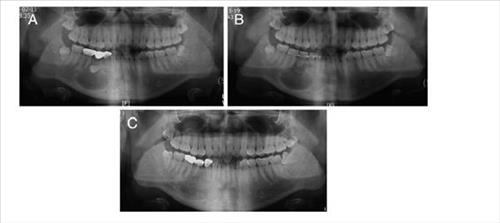

ÀÕ¸ö»À ¾ø´Â ȯÀÚ¿¡°Ô ÀÚ°¡Ä¡¾Æ ÀÌ½Ä ¼º°ø